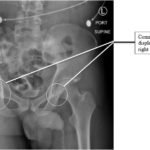

The initial radiograph of the pelvis revealed bilateral hip dislocations. Small bony fragments were noted in the right hip joint, suggestive of an underlying fracture. The sacroiliac joints and the pelvic ring were intact. In the emergency department, bilateral hip reductions were performed using the Captain Morgan technique.1 The post-reduction film showed reduction of the bilateral hip dislocations with extensive comminuted and displaced fractures of the right and left acetabula.